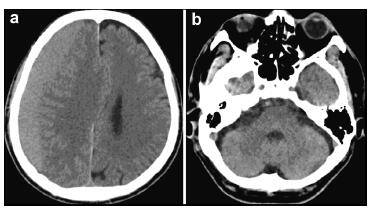

20170712151100  Figure 1 Preoperative computed tomography images of the brain show a right side subdural hematoma without abnormal findings in the posterior fossa and right side frontal lobe.

20170712151136  Figure 2 Computed tomography images obtained after surgery (a, b: 60 hours; c, d: 4 days; e, f: 7 days; g, h: 11 days; i, j: 19 days).